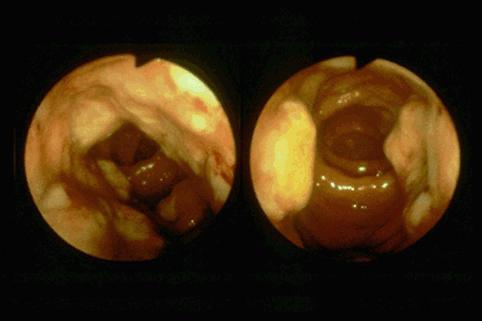

疾患(病理主体)の分類炎症性・潰瘍性疾患/アメーバ赤痢

部位(臓器別)大腸/2区域以上の大腸にまたがるもの

検査方法内視鏡

病変の最大径(ミリ)40以上